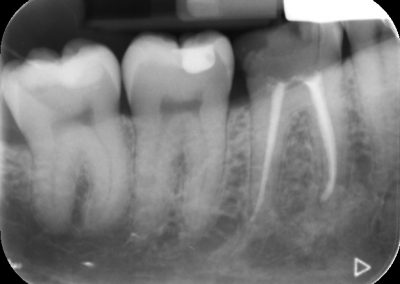

Files of different sizes are used to eliminate bacteria and infection and to shape the canals. The canals are disinfected thoroughly with irrigants and later the canals will be sealed in 3 dimensions with a special medicament called gutta-percha to prevent reinfection of the tooth and the access cavity will be sealed with a temporary filling.

After a few weeks, the tooth will be checked and when all the infection has cleared, a crown will be usually required to protect the restore the tooth to function.

Studies have shown thorough cleaning with instruments, disinfection and sealing the canals contribute to the successful healing of the infection and this success is reported as 95%.